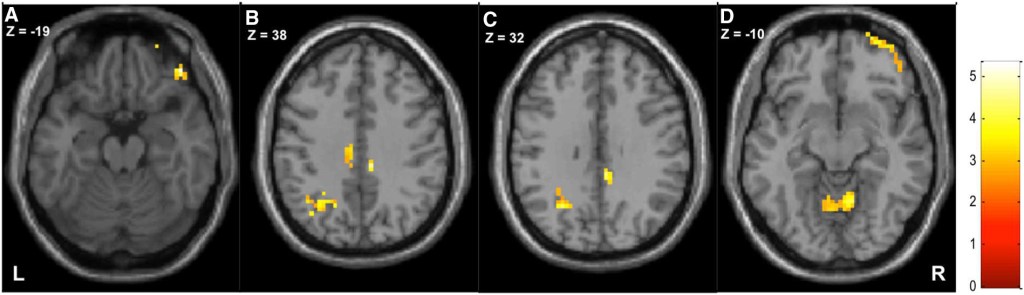

fMRI en FNS

Een test waar je tegenwoordig veel over hoort is de fMRI. De f staat voor functionele. Het verschil tussen een MRI en fMRI is dat de gewone MRI een ‘foto’ is van 1 moment waarop je niets doet, en de fMRI zijn eigenlijk 2 ‘foto’s’: 1 terwijl je niets doet en 1 terwijl je wél iets doet, terwijl je dus actief/functioneel bent. Op de fMRI maken ze zichtbaar op welke plek in de hersenen er activiteit is. Bij FNS kan dit betekenen dat je een fMRI krijgt terwijl je geen klachten hebt en wanneer je arm trilt. Of een fMRI terwijl je je goede arm beweegt en een fMRI terwijl je je verlamde arm probeert te bewegen. Die 2 fMRI’s vergelijken ze met elkaar en met fMRI’s van gezonde mensen. Ze hebben nu al kunnen zien dat de hersens van mensen met FNS op compleet andere plekken actief zijn dan bij gezonde mensen. Er is dus bewijs dat FNS-hersens anders werken.

De fMRI is moeilijk om te maken en wordt voor onderzoek gebruikt. Het wordt niet gebruikt voor het stellen van de diagnose. Dat is ook niet nodig, er zijn veel andere manieren om de diagnose te stellen.